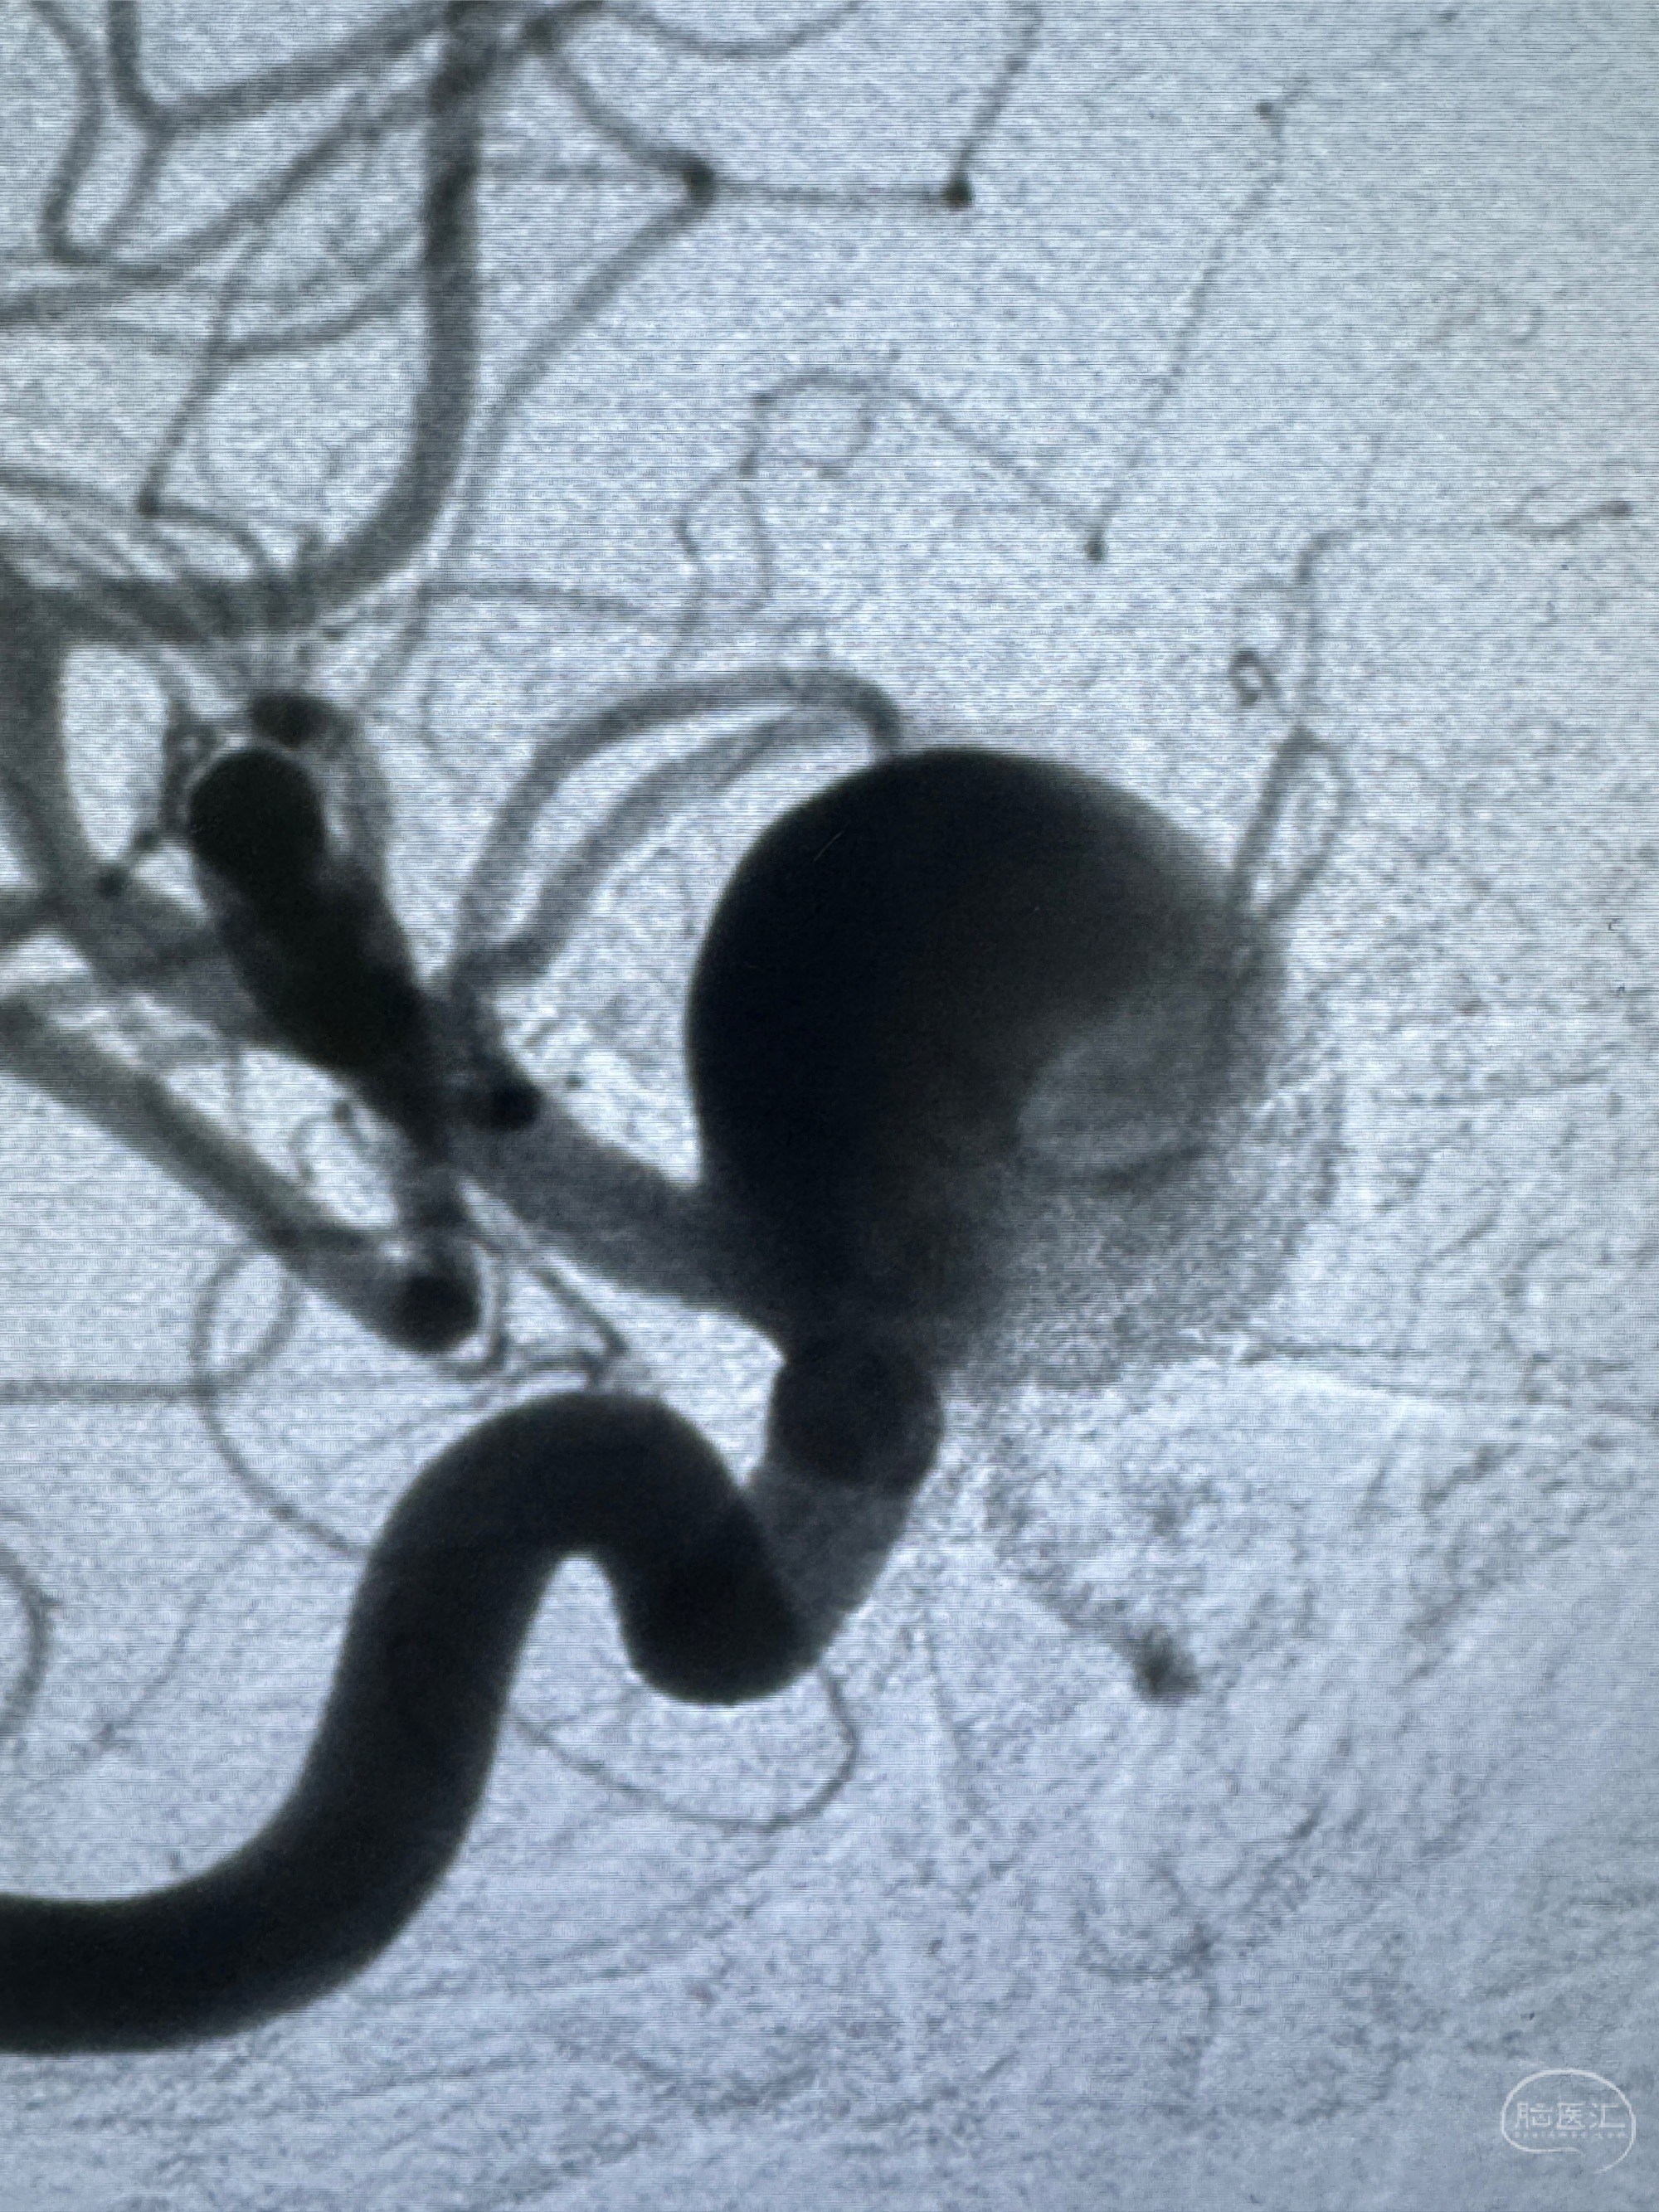

旋转3D展示动脉瘤局部的血管构筑

测量动脉瘤的大小:16*13.8*7.6mm大小,较原先变大,考虑双抗后瘤内血栓溶解可能

观察动脉瘤腔内的血流动力学情况

密网支架微导管在微导丝引导下超选择性插入右侧大脑中动脉

切换到动脉瘤瘤颈的角度,栓塞导管塑形后引入动脉瘤内